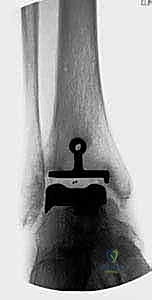

1. نظام سالتو لمفصل الكاحل الكلي (Salto Total Ankle Prosthesis - Mobile Bearing)

مفصل سالتو الأصلي هو ثمرة أبحاث أوروبية مكثفة. تم تطويره بين عامي 1994 و 1996، وبدأ استخدامه السريري بنجاح باهر في يناير 1997.

* التصميم الميكانيكي: يُعرف بأنه نظام ذو "مكون متحرك" (Mobile-bearing). يتكون من ثلاثة أجزاء رئيسية:

1. مكون معدني يثبت في أسفل عظمة الساق (Tibia).

2. مكون معدني يثبت في أعلى عظمة الكاحل (Talus).

3. قطعة بلاستيكية من البولي إيثيلين عالي الكثافة (Polyethylene insert): هذه القطعة ليست ثابتة، بل تنزلق بحرية بين المكونين المعدنيين.

* الميزة الكبرى: هذا التصميم يسمح بـ "التموضع الذاتي" (Self-alignment). أثناء الحركة، تتحرك القطعة البلاستيكية لتتكيف مع القوى الميكانيكية، مما يقلل من الضغط الواقع على واجهة التثبيت بين المعدن والعظم، ويحاكي حركة الكاحل المعقدة بشكل رائع.

* التثبيت: هو مفصل "غير إسمنتي". يتم تغطية الأسطح المعدنية الملامسة للعظم بطبقة مسامية من التيتانيوم وهيدروكسي أباتيت (Hydroxyapatite). هذه الطبقة تشجع العظم الطبيعي للمريض على النمو داخل مسام المفصل (Bone Ingrowth)، مما يوفر تثبيتاً بيولوجياً صلباً يدوم لسنوات طويلة.

2. نظام سالتو تالاريس (Salto-Talaris Prosthesis - Fixed Bearing)

بناءً على النجاح الهائل لنظام سالتو، تم تطوير نظام سالتو تالاريس لتلبية متطلبات مدارس جراحية مختلفة (خاصة في الولايات المتحدة).

* التصميم الميكانيكي: يشارك هذا النظام نفس الهندسة التشريحية الممتازة للمكونات المعدنية لنظام سالتو، ولكن مع اختلاف جوهري واحد: المكون البلاستيكي (البولي إيثيلين) هنا ثابت (Fixed-bearing) ويتم قفله بإحكام داخل المكون المعدني العلوي (الظنبوبي).

* الفلسفة وراء التصميم: أثبتت الأبحاث وخبرة الجراحين، بما في ذلك الأستاذ الدكتور محمد هطيف، أنه إذا تم إجراء القصات العظمية أثناء الجراحة بدقة متناهية تتوافق مع التشريح الطبيعي، فإن الحاجة إلى حركة واسعة للمكون البلاستيكي تقل بشكل كبير.

* الميزة الكبرى: نظام سالتو تالاريس يوفر استقراراً